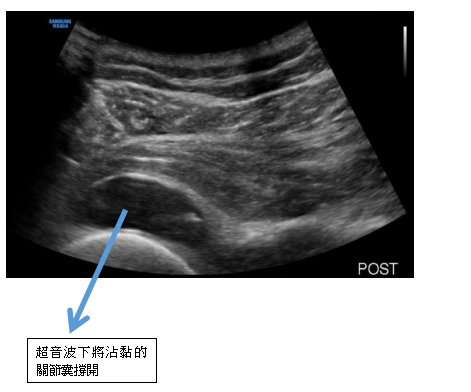

超音波下關節囊擴張

透過 及時超音波導引 與 治療中 神經阻斷止痛,能精準、安全地解除關節囊沾黏。